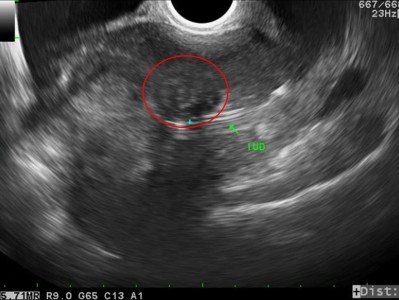

36歲的高小姐因為月經血量異常,輾轉來到花蓮慈院求診,經過門診子宮腔鏡檢查,才發現長了一顆約三公分的肌瘤,由於生長部位較為深層,所以,在其他醫療院所透過超音波並沒有明確發現肌瘤的存在,後續也藉由子宮腔鏡內視鏡手術,無傷口刮除肌瘤,陳萱醫師表示,經過切片檢查,證實為良性肌瘤。

陳萱醫師表示,子宮肌瘤是婦女常見的疾病之一,最常見的症狀就是月經大量出血或者點點滴滴來個不停等經血異常。而超音波檢查其實就有機會可以檢查出子宮肌瘤,只是有些肌瘤就像是高小姐一樣,生長在較深的肌肉層或漿膜層,不容易被發現,但是透過子宮腔鏡檢查就可以發現,進而早期治療。

圖:經過包含子宮腔鏡在內的檢查,陳萱醫師發現造成高小姐困擾的就是子宮內的肌瘤。